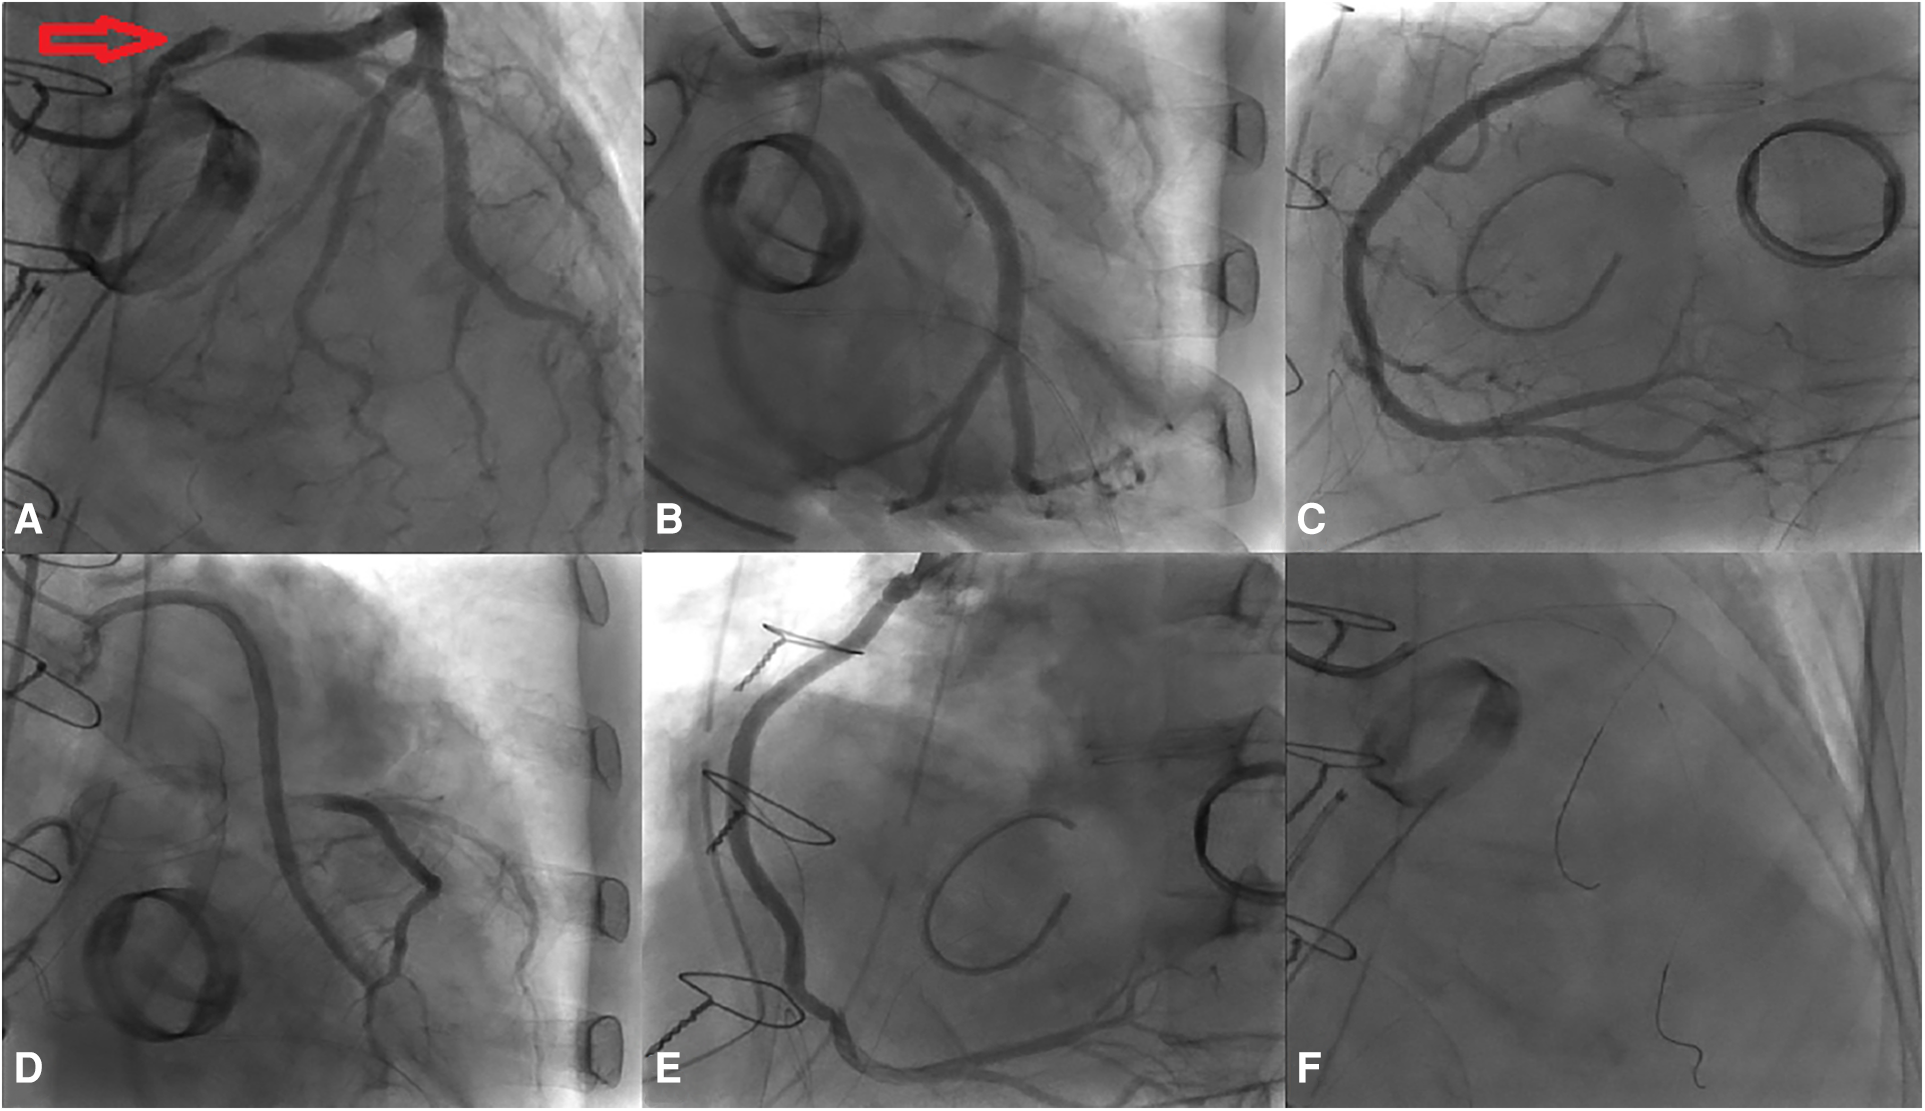

A 4.0 × 24 mm drug-eluting stent (DES) was deployed in the LMCA-LCx, followed by post-dilation of the LMCA stent segment using a non-compliant (NC) balloon measuring at 5.0 × 15 mm. Subsequently, the sion blue wire was re-wired to the distal LAD, and the ostium of LAD was dilated with a 3.0 × 20 mm NC balloon. Following the initial post-dilation within the stent with a 4.0 × 20 mm NC balloon, second post-dilation was performed on the LMCA stent segment using a 5.0 × 15 mm NC balloon. Post-procedure coronary angiography confirmed TIMI 3 flow in the LMCA and LCx (Figure 4).

Figure 4. The PCI procedure for the LMCA and the LCx. (A) Deployment of a DES in the LMCA-LCx. (B) Initial Proximal Optimization Technique (POT) in the LM using a NC balloon. (C) Subsequent rewiring and dilation of the LAD ostium with a NC balloon. (D) In-stent post-dilation. (E) Second POT in the LMCA. (F) Final angiographic result.